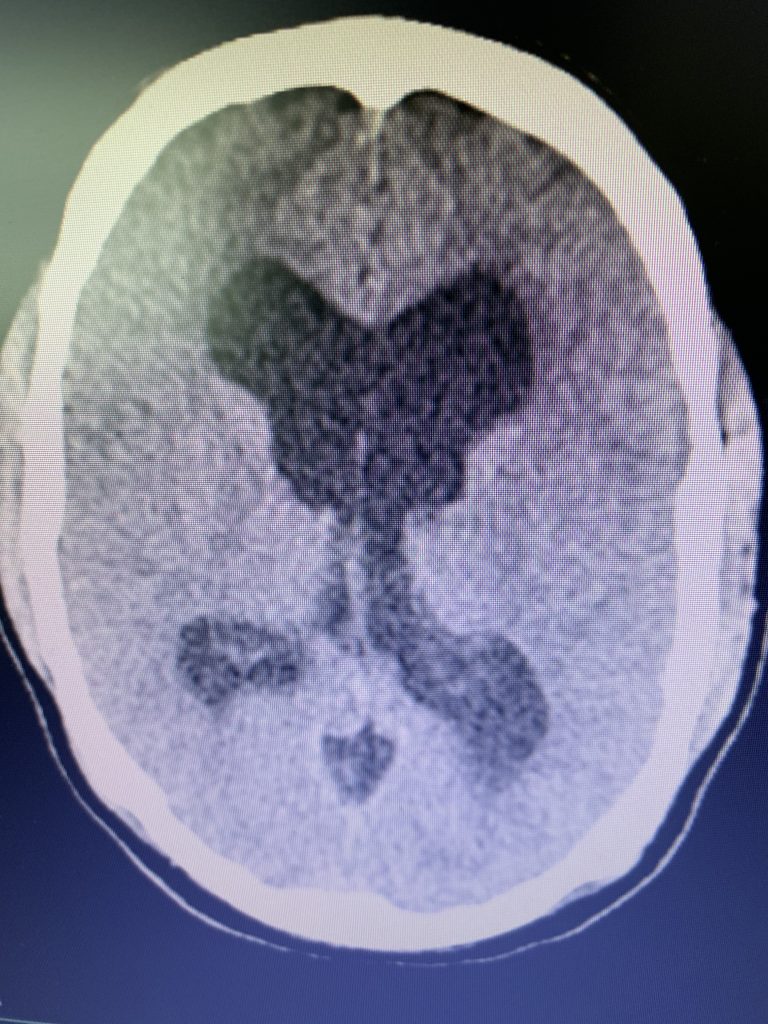

Figure 1B,C: Pre-operative CT images.

Prior to shunting, a head CT was obtained and the head CT in addition to documenting a patten of obstructive hydrocephalus suggested a possible mass lesion compressing the aqueduct at its inferior aspect. Figure #1 demonstrates the hydrocephalus and the possible lesion. A decision was made at this point that the patient had obstructive hydrocephalus that was now symptomatic and he was taken for a laparoscopic-assisted ventriculoperitoneal shunt.